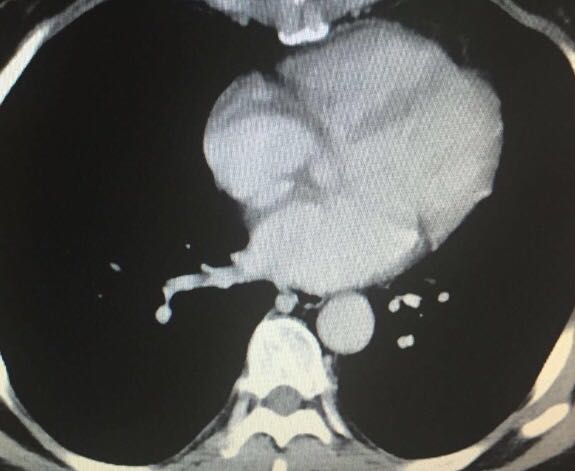

妇科查体:外阴发育正常,阴道畅,粘膜无充血,分泌物少,无异味,宫颈光滑,萎缩。子宫增大,形态不规则,宫体后可及近20cm大小实性肿物,活动度差,无压痛,双附件区增厚。 盆腔彩超:子宫水平位,大小约9.4*6.7*6.7cm,子宫内膜厚约0.9cm。宫腔内可见节育器反射。右前壁见5.7*6.3*5.4cm低回声团,边界清楚。盆腔子宫周围双附件区可见多发实性肿物相互融合,范围约16.6*18.8*8.0cm,形态不规则,内呈低回声,CDFI可检出血流信号,肿物与子宫分界不清。盆腔未见明显游离液体。

诊断 : 子宫肌瘤; 行开腹探查,见:子宫明显增大,形态极不规整,可见多个肌瘤结节,分叶状,质极软,较大者直径15厘米,并有多个肌瘤向双侧阔韧带内生长,占据整个盆腔,右侧延伸至盆底,并与肠管,膀胱粘连。双侧附件未见异常。行全子宫切除,术后病理:子宫多发平滑肌瘤,伴变性。子宫腺肌症。